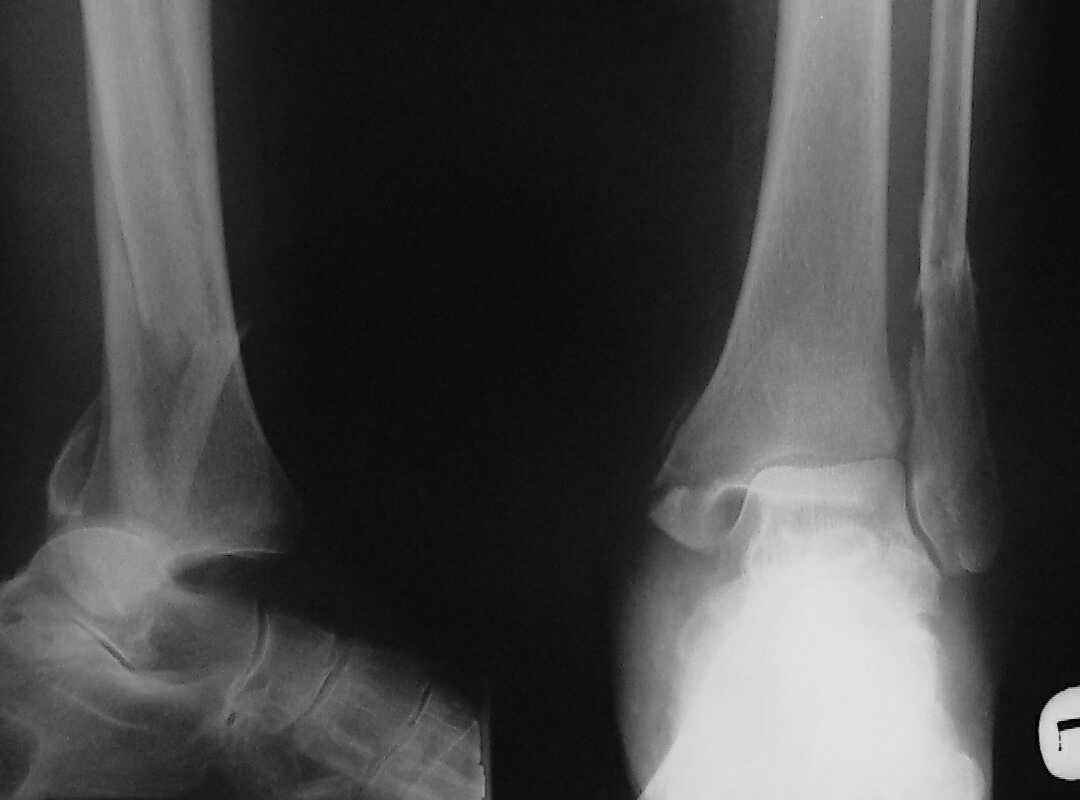

Больная 1936 г.,травма 15 ноября 2003,закрытый трехлодыжечный перелом г/стопного сустава, сахарный диабет.

При поступлении - закрытая репозиция, повторная в связи с большим отеком через неделю, подготовлена к остеосинтезу в первых числах декабря. Заживление без осложнений. Циркулярный гипс - 7 недель, снят,часть спиц удалено 20 февраля т.к.пальпировались под кожей, постепенная нагрузка, проблем нет до середины апреля когда появильсь боли с мед. стороны сустава и локалная гиперемия ( трактовалась как флеботромбоз). Повторное поступление 15 апреля - усиление болей,пов. температура, локально выраженная гиперемия.Локально выделений нет. На RTG - деструкция в области мед лодыжки и заднего края. Сахар крови умеренно повышен. Как трактовать проблему, какой диагноз и тактика лечения? Заранее спасибо, Владимир.

Диагноз я бы поставил: неправильно срастающийся перелом обеих лодыжек и заднего края ББК. Ложный сустав мед. лодыжки? Хронический вялотекущий остеоимиелит голеностопа. Сопутствующий - СД, диабетическая ангиопатия 2.

Ретроспективно, на Ваш взгляд, что изменилось бы при остеосинтезе более массивными имплантами?(выбор в пользу спиц как раз и был из-за минимального объема оставляемых имплантов) Иммобилизация 7 недель это очень длительно? Результат на 4 RTG - в чем нефункциональность? - согласен, что репозиция заднего края не была достигнута. Какие признаки ложного сустава мед. лодыжки ?